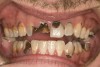

Joe soon learned how to manufacture the drug. His need for meth soon consumed his every thought. He basically lived to do more meth. He admitted that he had made some poor choices. Unfortunately once the addiction kicked in, he no longer had a choice, he had to use. This was his end result (Figure 4 through Figure 6). From these photographs, one might think that he had used the drugs his entire life; however, this progression happened over the course of only about 1 year of smoking the drug. Because of the caustic chemicals (muriatic acid, hydrochloric acid, lithium, etc) his teeth started to blacken, then break.

Figure 5  PRESENTATION CONDITION By the time Joe presented for treatment after serving time in prison and going to rehab, his teeth were completely destroyed by rampant decay. Although some teeth could have been saved, the patient chose to have all of the remaining teeth extracted in order to receive a set of full dentures.

Figure 5

Figure 6  PRESENTATION CONDITION By the time Joe presented for treatment after serving time in prison and going to rehab, his teeth were completely destroyed by rampant decay. Although some teeth could have been saved, the patient chose to have all of the remaining teeth extracted in order to receive a set of full dentures.

Figure 6